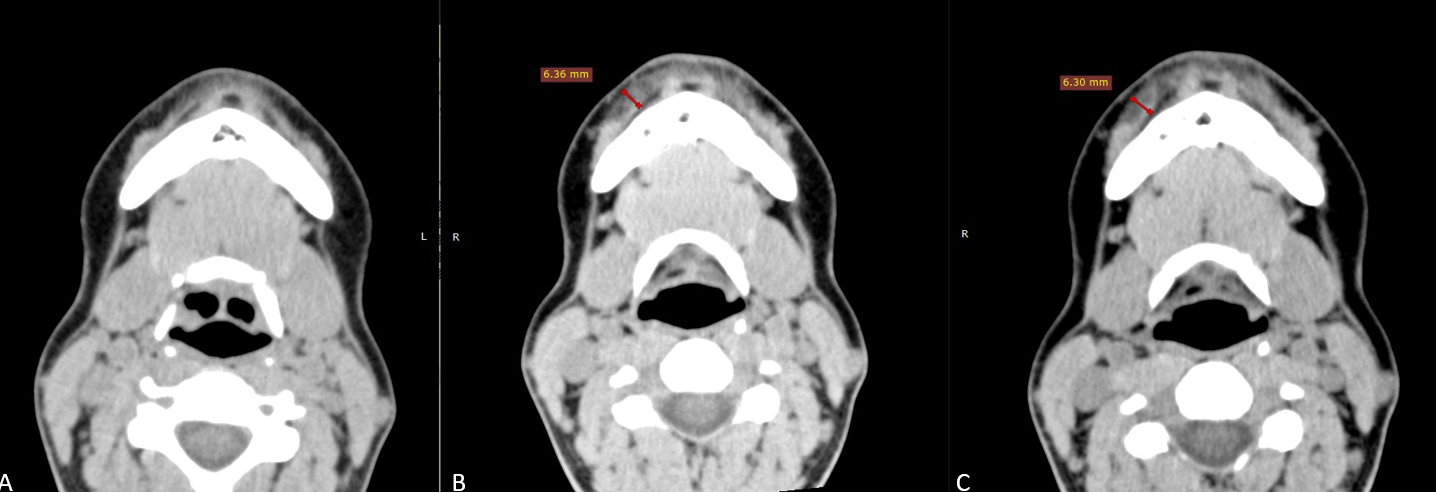

На аксиальных срезах подбородочной области (рис. 10) в мягких тканях губно-краевой области справа и слева визуализируется наличие филлера толщиной до 6.3мм, интимно прилежащим к мышце, опускающей нижнюю губу.

Рис.10

МСКТ сканы подбородочной области, аксиальная проекция

А – до инъецирования

В – сразу после инъецирования, толщина имплантата 6,4 мм

С – через 3 недели, толщина имплантата 6,3 мм

В динамике миграции препарата, реактивных изменений окружающих структур и признаков инкапсулирования не выявлено.

Отмечается появление более четких контуров, формирование гомогенной структуры, а также нивелирование инфильтративных изменений ПЖК посттравматического характера к 21 дню.